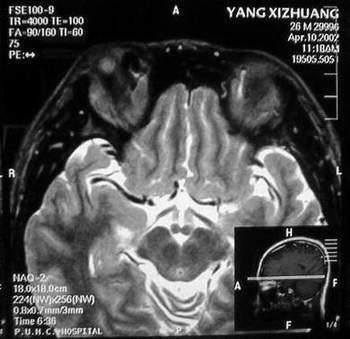

杨某,男,27岁。主因右眼进行性眼球突出一年。我院门诊就诊。发病来,患者无明显视物模糊,无视物成双。自觉无明显眼痛。五年前曾有食物中毒史。当地医院行CT检查,发现右眼眶鼻上方较高密度占位。

门诊检查:视力:双1.5。双眼各方向运动正常。右眼球向正前突出,其中颞侧更明显。右眼穹隆部结膜及近穹隆结膜血管扩张。右鼻上眶缘触及较饱满类结节物,压痛可疑。没有触及博动,听诊未及血管杂音。压迫颈静脉眼球凸度无明显改变。

B 超:球内未见明显异常回声,眶内可见血管暗影回声,视神经上下眶内周围软组织可见各一个血管暗影腔,眶内可见回声不均匀中度密度占位样回声。IMP: 眶内炎性病变?建议MRI除外动静脉瘘,血管性病变。

MRI及增强结果如下:

患者压颈及其它Valsava试验结果阴性。从MRI分析,在T1、T2、T+C检查该支血管均为明显流空现象,说明该血管血流速度很快,而从走行和分布看,眼上静脉可能性很大。也许也不能除外异常的眼动脉或异常血管。眶内主要可能的血管病变包括颈内动脉海绵窦瘘(高流窦)、AVM、眼眶静脉曲张、海绵状血管瘤、静脉性血管瘤、毛细血管瘤和眶内动脉瘤。。